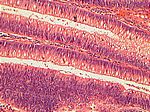

Polyp. Dickdarmadenom, HE